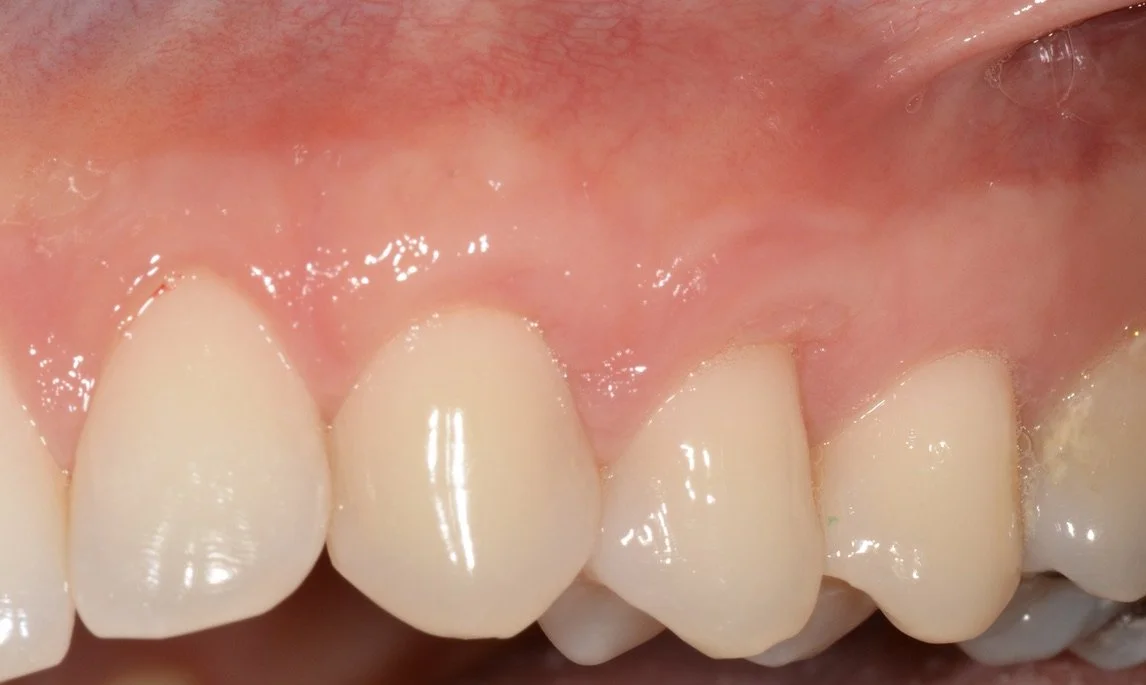

Objectif : Augmenter la quantité de gencive attachée et recouvrir des racines dentaires exposées.

• Sensibilité dentaire

• Inesthétique

• Progression des récessions

• Manque de gencive